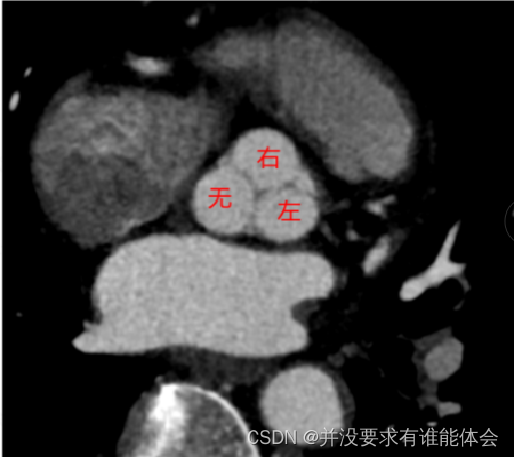

冠脉解剖-起源

冠状动脉通常起源于主动脉冠状动脉窦,右冠状动脉起源于右冠状窦(位于前方),左冠状动脉干起源于左冠状窦(左后方)

无冠状窦:(右后方)